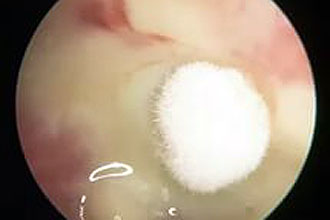

Микозы ушной раковины

Микозы — это грибковые инфекции. Кожа ушного канала и ушной раковины может подвергаться микозу, если человек чрезмерно очищает слуховой проход от серы. Также отомикозом могут страдать пациенты с сахарным диабетом.

Отомикоз может развиться в процессе лечения отита. Это происходит потому, что спиртовые капли для ушей (борный и фурацилиновый спирт), а также капли с антибиотиками уничтожают бактерии в слуховом проходе. Хотя это помогает в лечении отита, оно может привести к неконтролируемому размножению грибков. Бактерии и грибки — постоянные соперники: когда одни уничтожаются, другие получают возможность беспрепятственно колонизировать поверхность кожи.

Крайне важно соблюдать дозировку и продолжительность курса лечения при использовании антибактериальных капель для ушей. В противном случае на фоне терапии может развиться отомикоз.

При отомикозе пациента беспокоит зуд, налет или выделения желтого или черного цвета, а также шелушение в ушах. Лечение включает использование капель или мазей для ушей с противогрибковым эффектом, таких как Миконазол или Клотримазол. В некоторых случаях назначаются противогрибковые препараты общего действия, которые ускоряют процесс выздоровления, например, Флуконазол или Кетоконазол в форме таблеток.